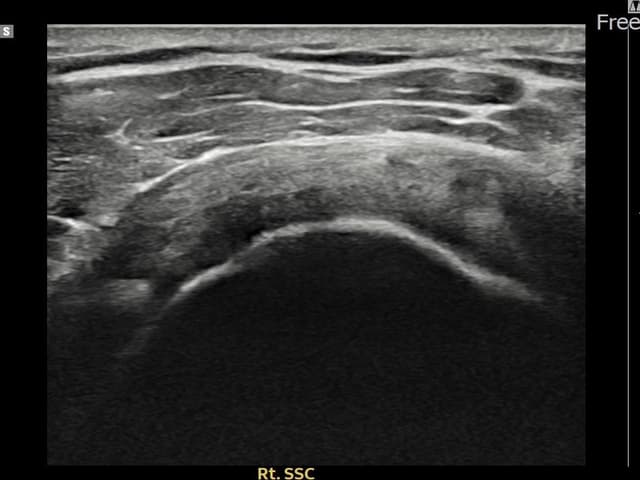

右侧 견갑하근건 关节面侧部分撕裂

7mm × 3mm (肌腱厚度约28%缺损)